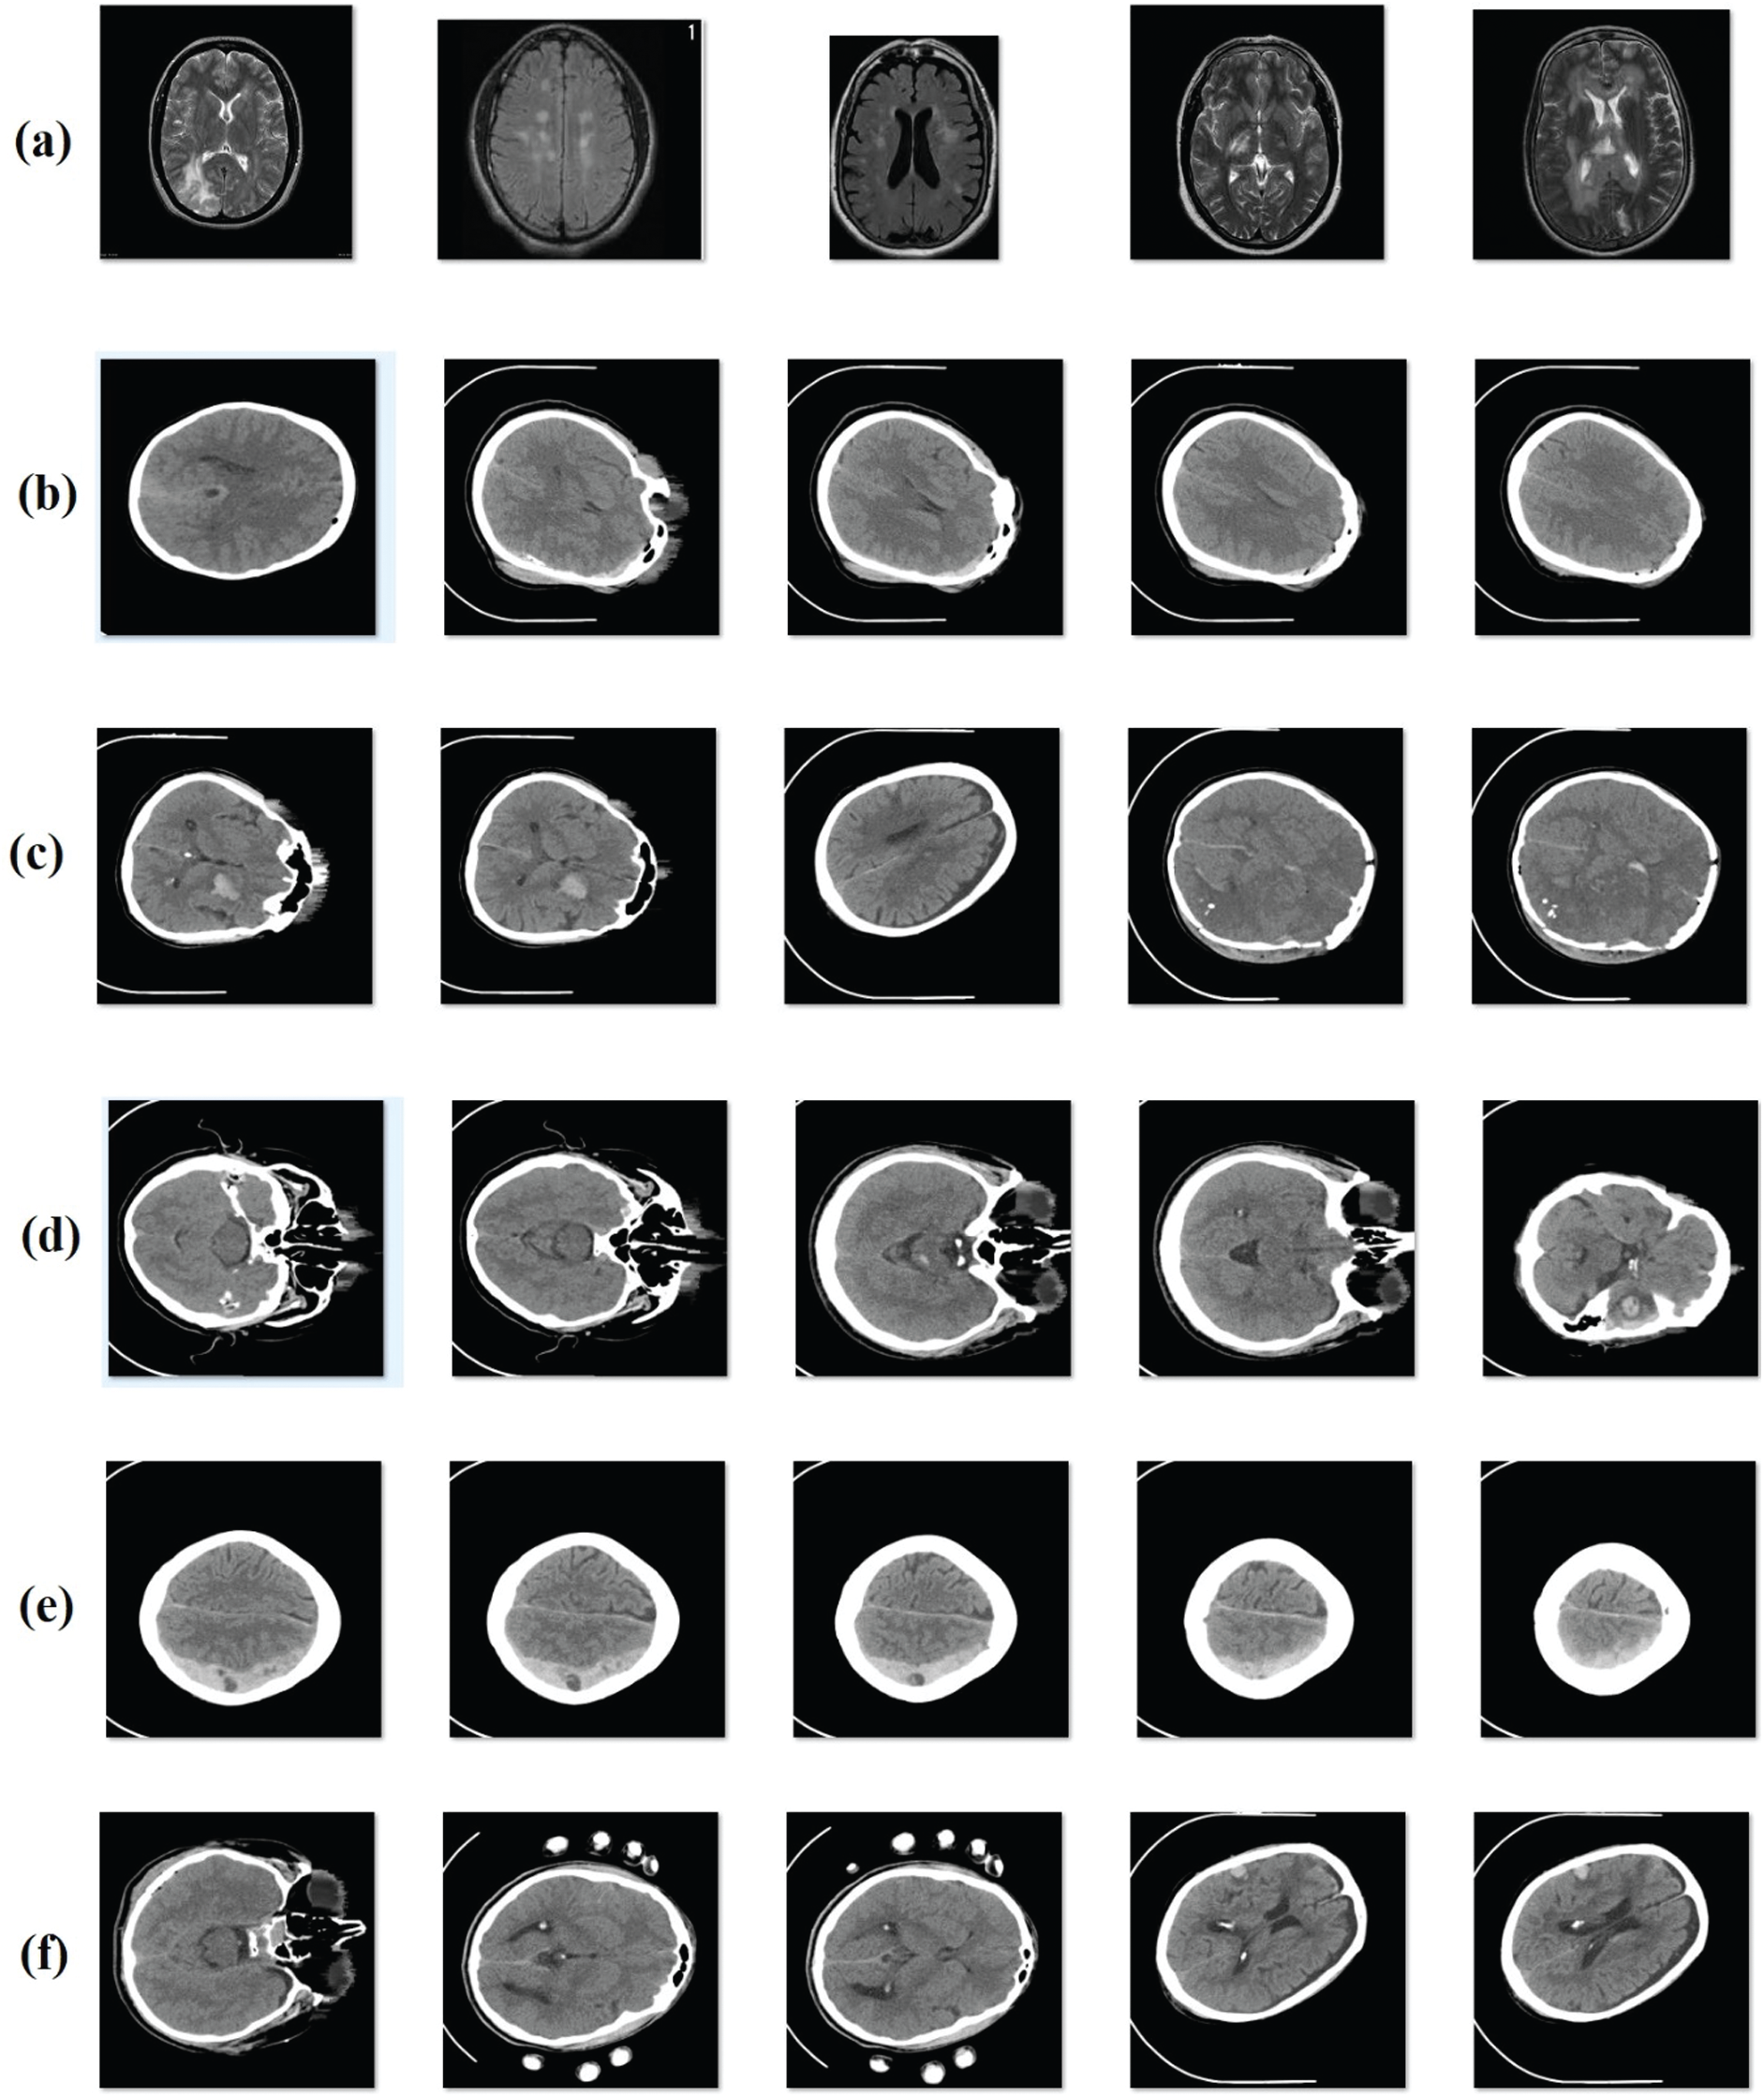

Figure 4: Sample images (a) no hemorrhage (b) epidural (c) intraventricular (d) intraparenchymal (e) subdural (f) subarachnoid

In order to evaluate the performance of the proposed model, an experimental analysis was conducted using a standard ICH dataset [17]. Fig. 4 depicts the sample group of images showing different classes of ICH. CT scan images dataset was collected from 82 patients under the age group of 72 years. Moreover, the dataset is composed of images grouped under six classes, such as Intraventricular with 24 slices, Intraparenchymal with 73 slices, Subdural with 56 slices, Subarachnoid with 18 slices, and No Hemorrhage with 2173 slices. Simulation outcomes were measured in terms of four parameters, such as sensitivity (SE), specificity (SP), accuracy, and precision. To perform the comparative analysis, different methods were used such as U-Net [18], Watershed Algorithm with ANN (WA-ANN) [19], ResNexT [20], Window Estimator Module to a Deep Convolutional Neural Network (WEM-DCNN) [21], CNN and SVM.